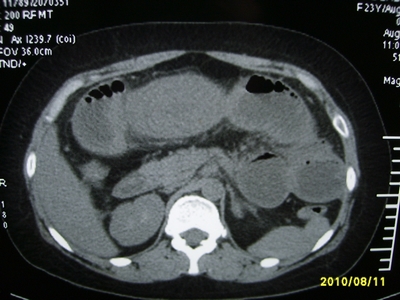

5天前突发腹痛剧烈难忍,伴解淡血水样便。近一天来腹痛缓解,没有明显的腹膜炎的体征。今天照的腹部ct。从ct上看感觉是一个绞窄性肠梗阻,但是现在没有腹痛。不好解释

请放射科的专家,帮帮看看。从影像学的角度来看看。这是不是一个绞窄性肠梗阻。

要有麻烦了,感觉小肠有套叠还有扭转改变,估计部分已有坏死。

高位肠梗阻(不全性),原因小肠(空肠)扭转,肠壁水肿增厚,成年人肠梗阻要排除合并占位,建议手术。

绞窄性肠梗阻_肠管套叠 扭转,肠壁明显水肿。

病人现在没有腹痛。怪了。从影像上来看。确实是绞窄了。但是没有腹痛。没有明显的腹膜炎的体征。确实有不好解释。难道是坏死了。反而不痛了。怪怪怪

支持绞窄性肠梗阻,肠壁明显水肿并见有多发小泡状积气--肠坏死

考虑绞窄性肠梗阻并肠坏死。